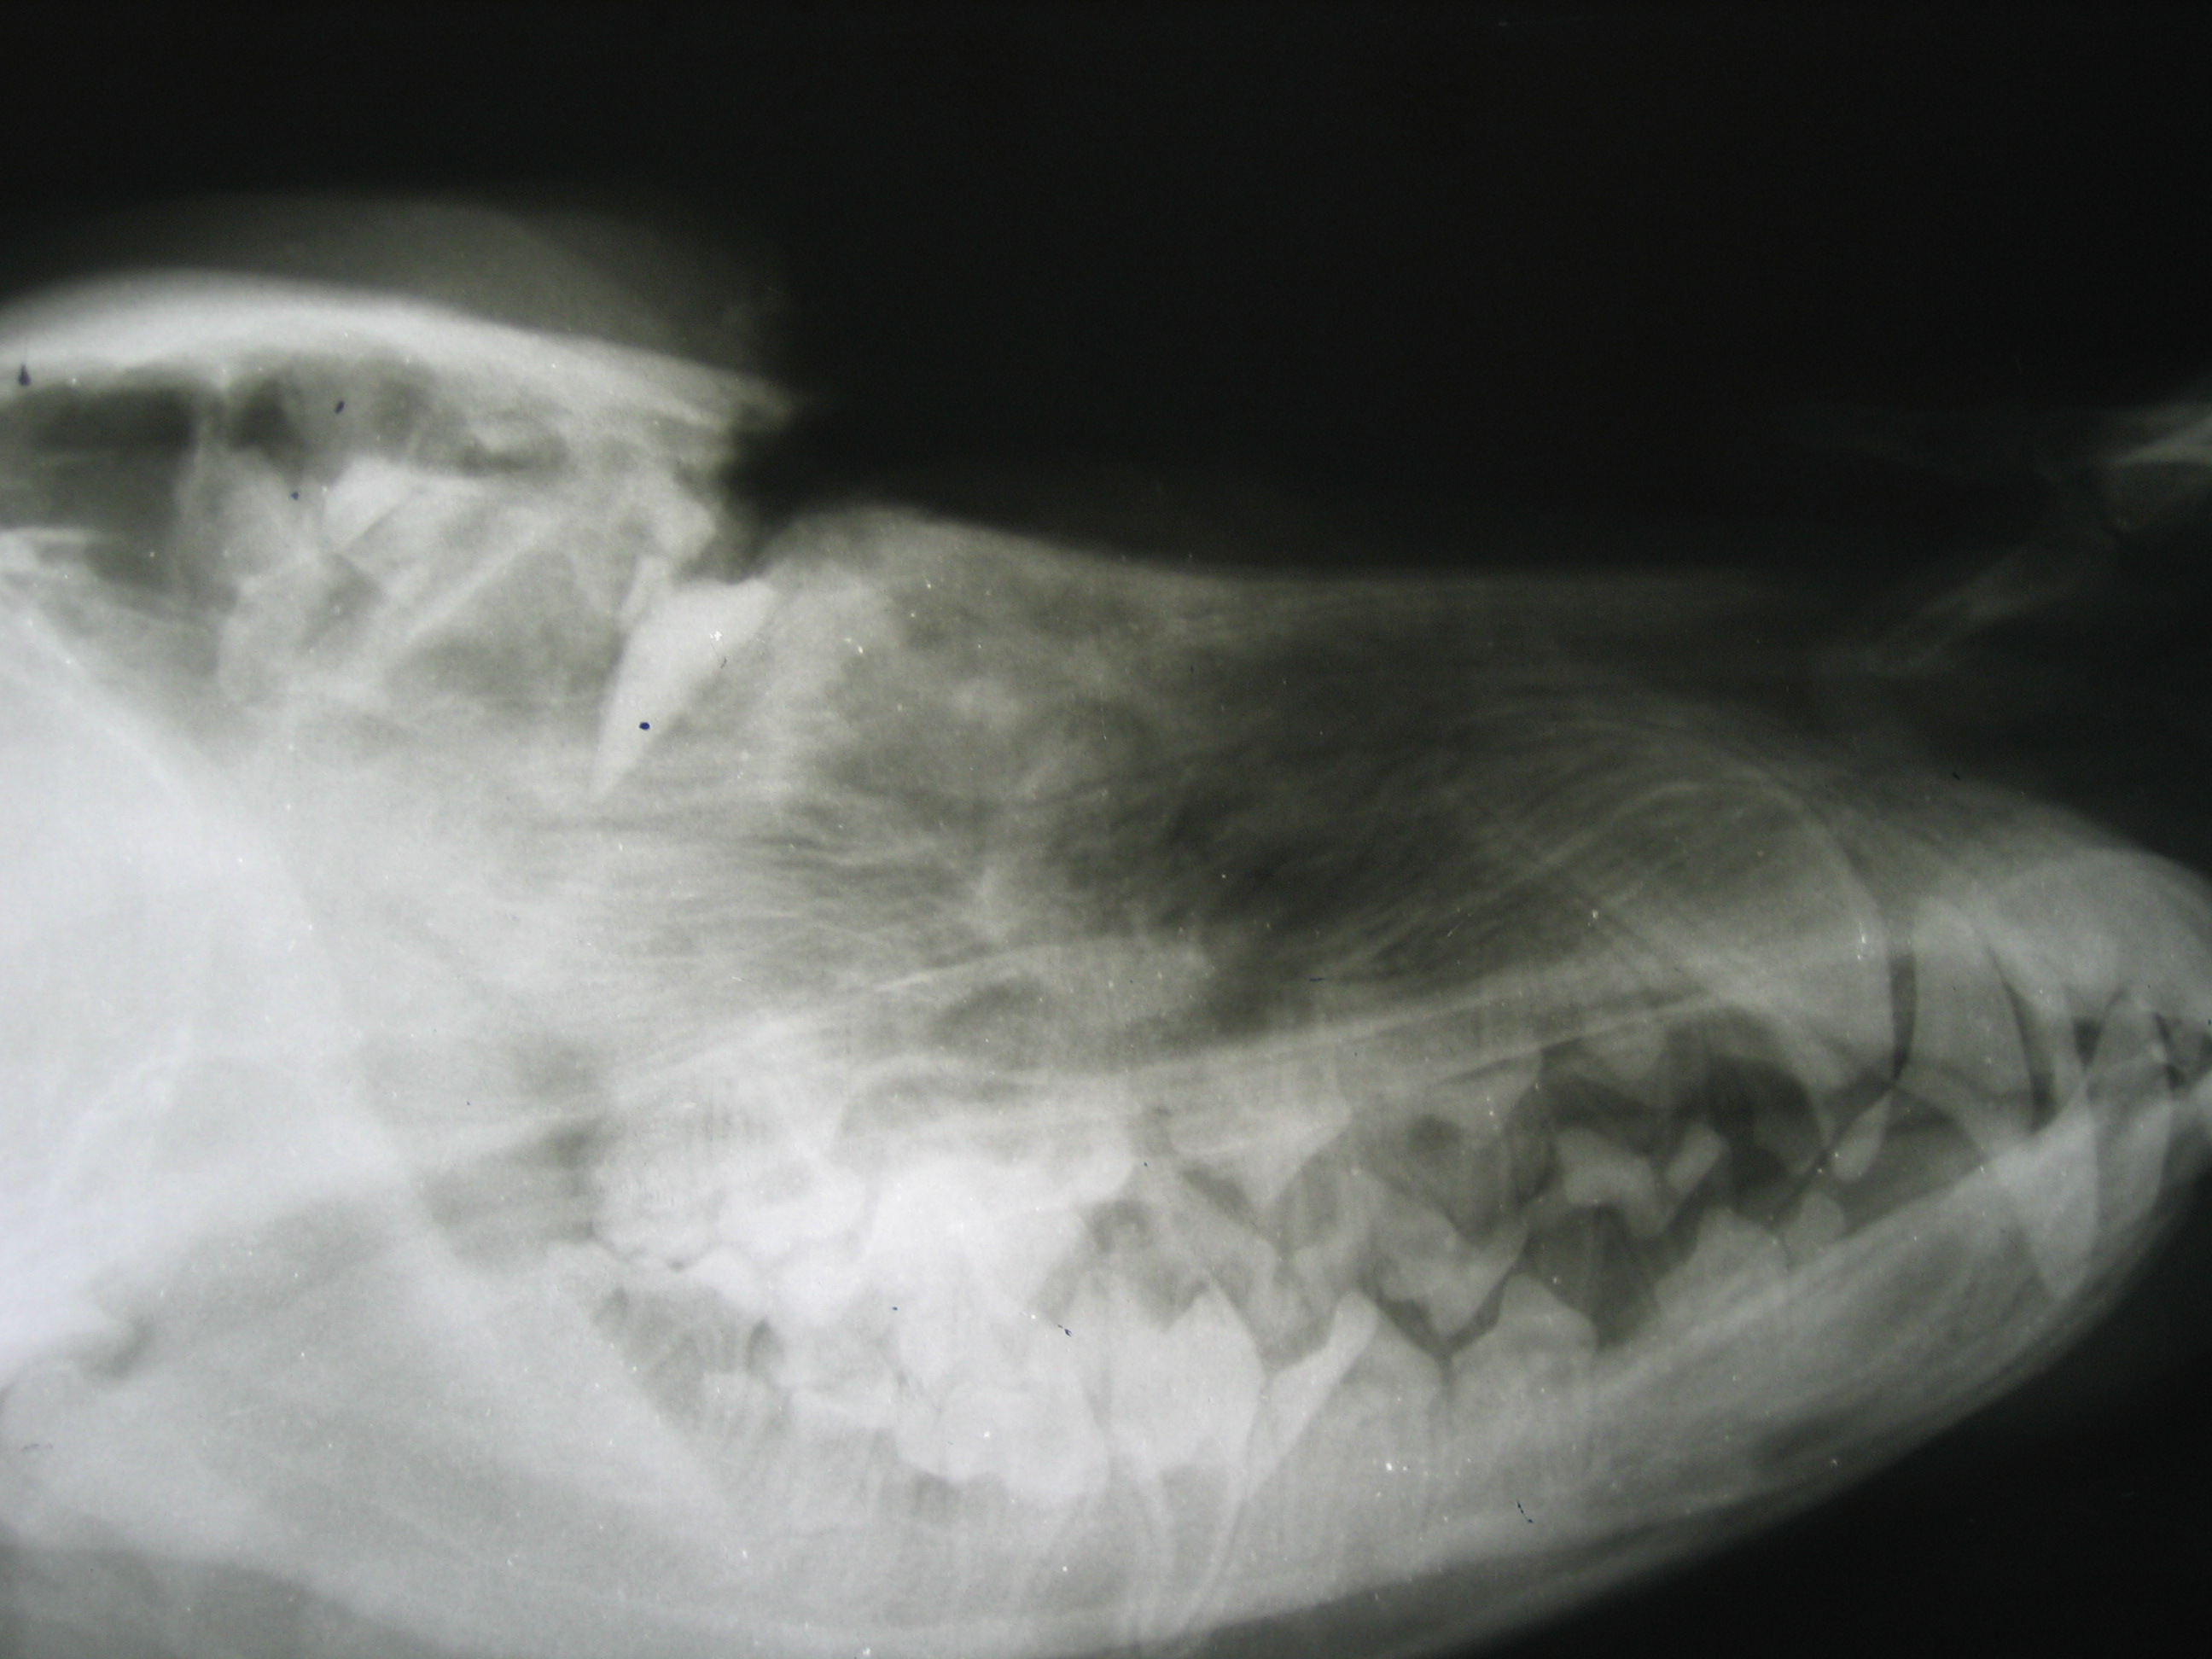

Есть две новости: хорошая и плохая. Хорошая - кобель у меня..... Плохая - кобель у меня в стационаре. 7 августа привезли случайные свидетели ДТП, в котором легковой а/м сбил собаку. Помимо пироплазмоза, который Матрос подцепил видимо скитаясь, у него были переломы 2 рёбер, разрыв селезёнки и проникающее травма костей черепа. Из головы были извлечены осколки фары. Глаза по счастливому стечению обстоятельств остались целы, веки сильно пострадали, через месяц назначена пластика одного века. Пса теперь зовут Лаки, после полного восстановления ему найден новый дом. Если Ева всё же захочет забрать пса - мы его конечно отдадим, но после беседы с владельцем.

Пёс бодр и весел, переломы срослись, селезёнку удалось сохранить почти полностью. Пластику век ему по большому блату))))) делала одна из лучших человеческих пластических хирургов Москвы (ФИО не пишу, чтобы не сказалось на репутации), параллельно уменьшили шрам от операции на морде. Сейчас по мере обрастания шерстью о травме не остаётся никаких напоминаний.

Пару фоток для размышления. http://fastpic.ru/view/64/2014/0905/7c4 ... e.jpg.html http://fastpic.ru/view/64/2014/0905/72b ... 2.jpg.html http://fastpic.ru/view/64/2014/0905/598 ... 4.jpg.html